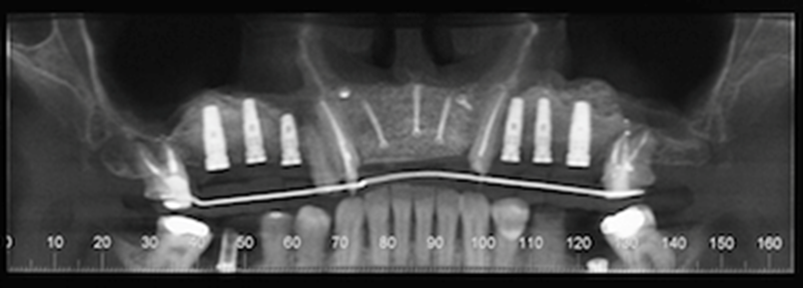

At the 8-months follow-up, a CBCT scan showed consolidation of the grafted material with the recipient bone (Figure 6). A second surgical procedure was conducted under local anesthesia and oral sedation in order to remove the titanium mesh. At this appointment, the pre-maxilla showed to be significantly augmented (Figure 7) with the dimension of 14 mm in height and 10 mm in width. The bone characteristics were soft, erythematous, with a cancellous texture. Four dental implants (Biomet 3I certain®, USA) were inserted, with no more than 25 Ncm2 of primary stability (Figure 8). The implants were uncovered 6 months later for initiation of the prosthetic rehabilitation using 4 single-unit crowns. One-year follow-up showed to be uneventful (Figure 9).

Figure 6.CBCT scan 8 months post ridge augmentation. Note significant increase in bone augmentation of the pre-maxilla. Presence of implants for sites #2, 3, 4, 11, 12 and 13 after right and left sinus lifts were performed.

Figure 7.Re-entry at 8-monthspost-op shows a clinically significantly augmented maxilla. Occlusal viewshows implants (Biomet 3I certain®, USA) # 7 and 10 placed.

Figure 8.Perspective view of the augmented pre-maxilla with implants(Biomet 3I certain®, USA) #7, 9, 10placed. and #8 beingplaced.